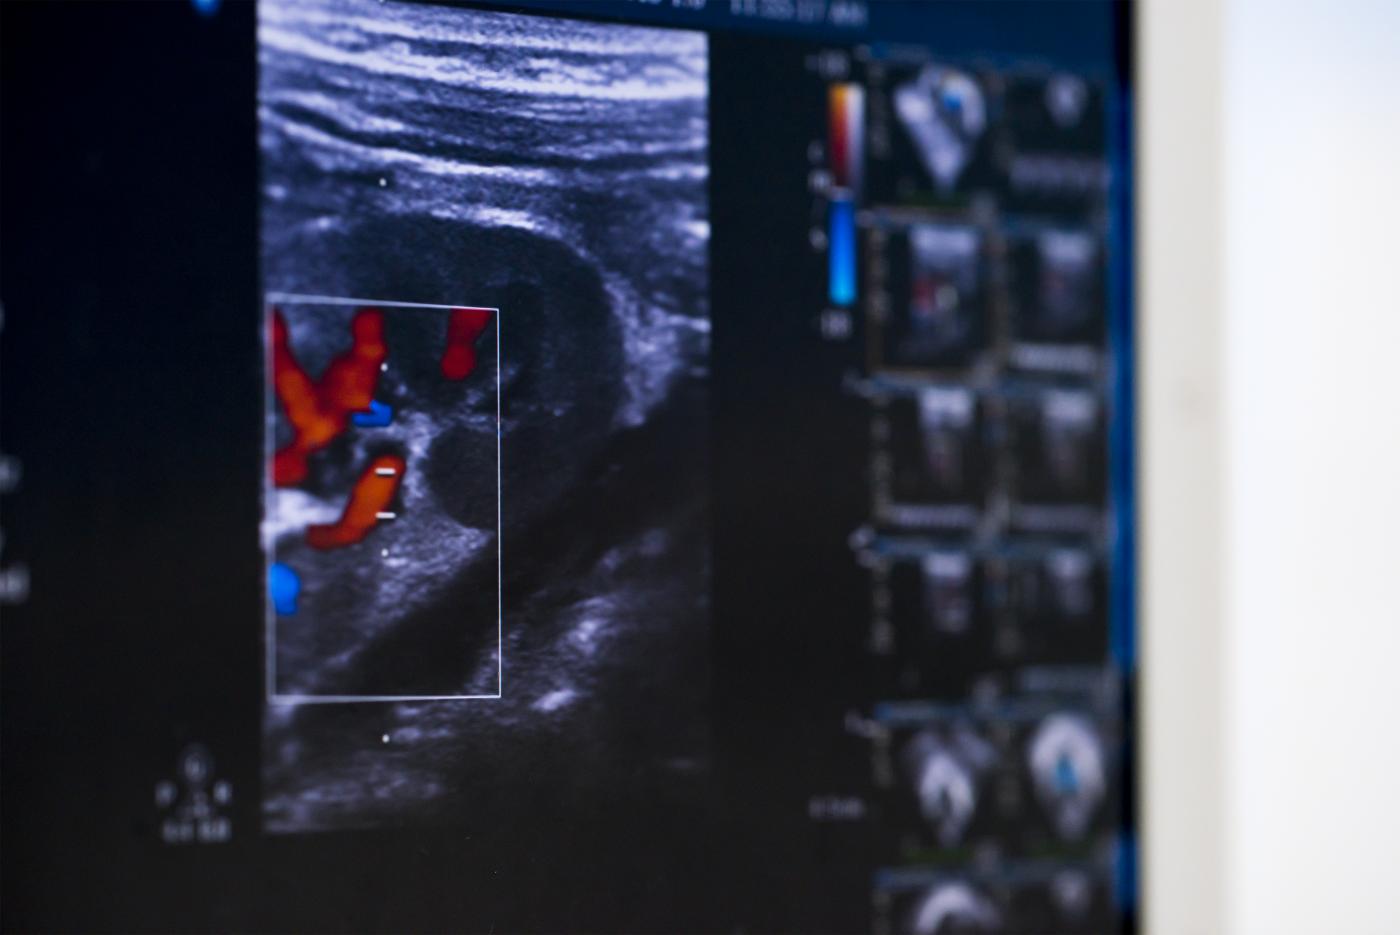

Estenosi aòrtica

És una malformació que es dona progressivament a la vàlvula aòrtica i produeix una obstrucció del flux de sortida del ventricle esquerre. Sovint, l’estenosi aòrtica va associada a més d’un tipus d’obstrucció, com ara l’estenosi de la vàlvula mitral, la coartació aòrtica i l’estenosi aòrtica supravalvular. Això fa que pugui formar part de la síndrome del cor esquerre hipoplàstic.